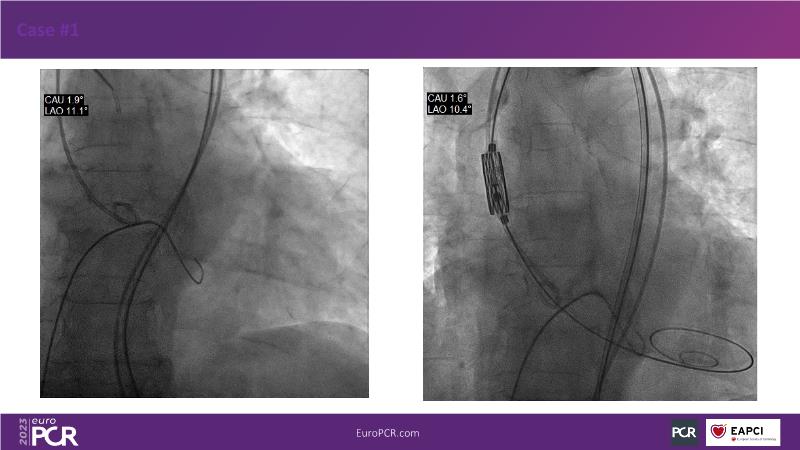

Join this session for an update on the science and clinical advancements in next-generation balloon-expandable transcatheter aortic valve replacement (TAVR) and thin strut bioresorbable scaffolds (BRS). Discover how these innovative technologies can improve clinical outcomes by exploring case-based challenging scenarios and learn effective strategies for tackling them.

- To highlight next generation transcatheter heart valve technologies that can contribute to better clinical outcomes

- To discuss case-based challenging scenarios and how to tackle them